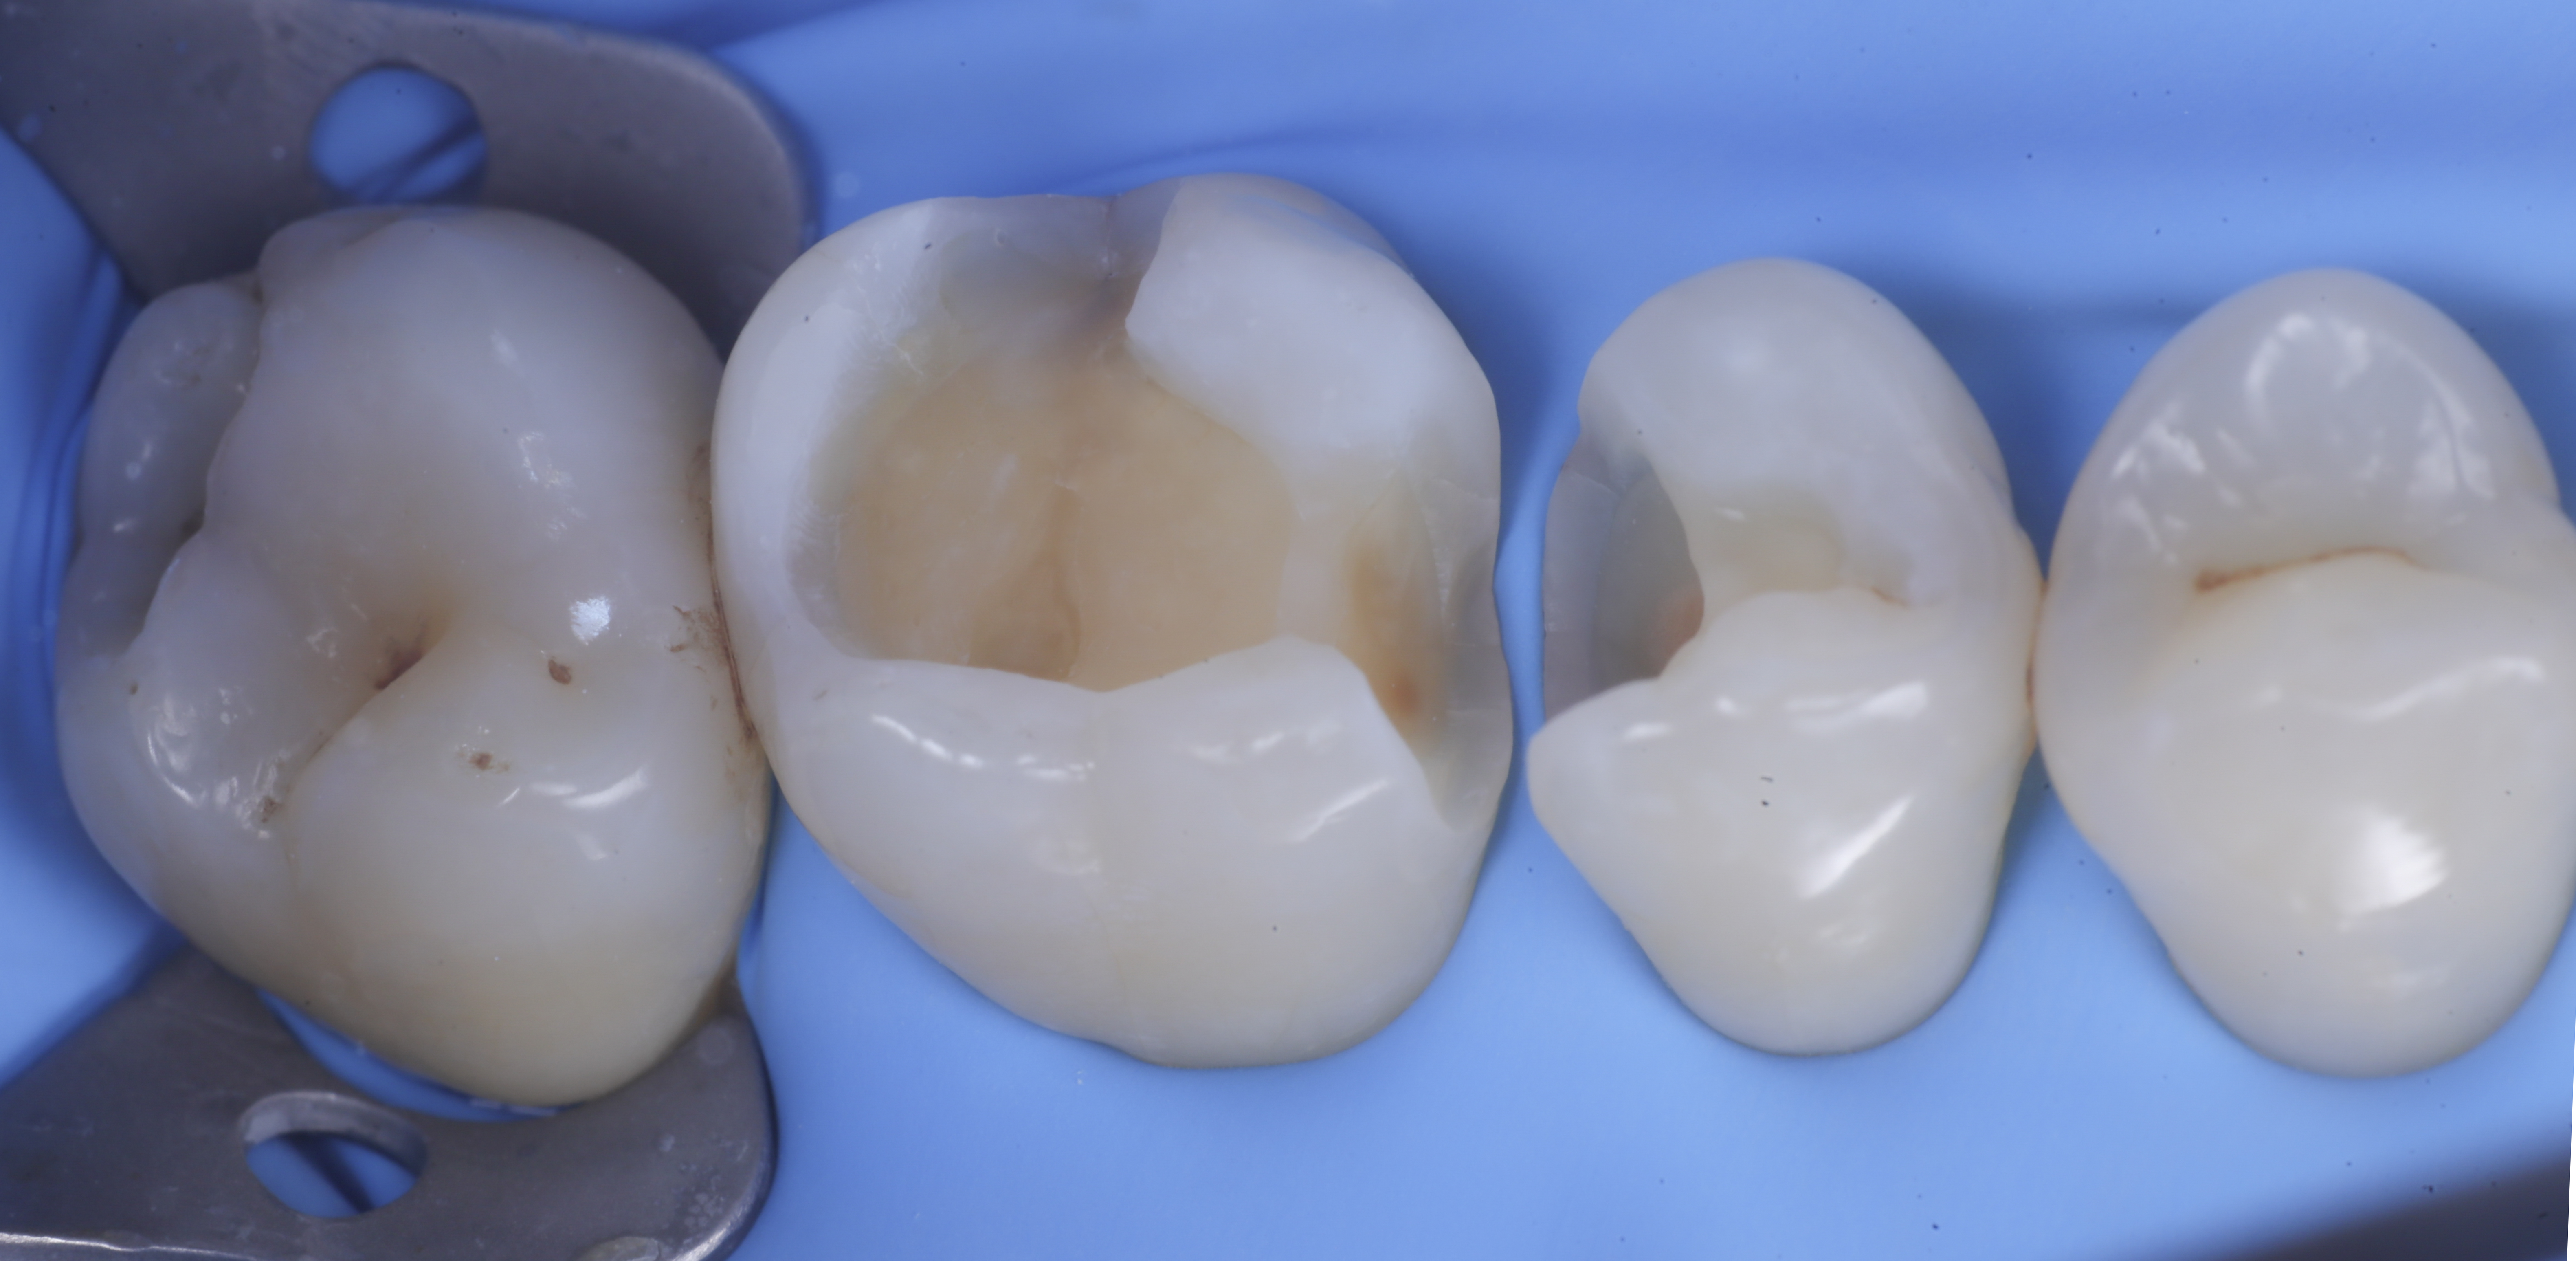

foto 1 Fotografia iniziale

foto 2 Isolamento e aspetto delle cavità ultimate